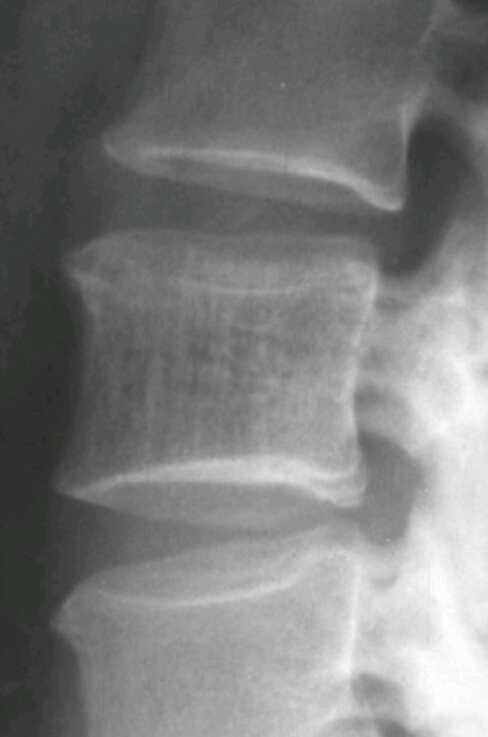

Findings? Diagnosis?

Exaggerated vertical trabeculations (honeycomb appearance), posterior bulge of cortex

Hemangioma